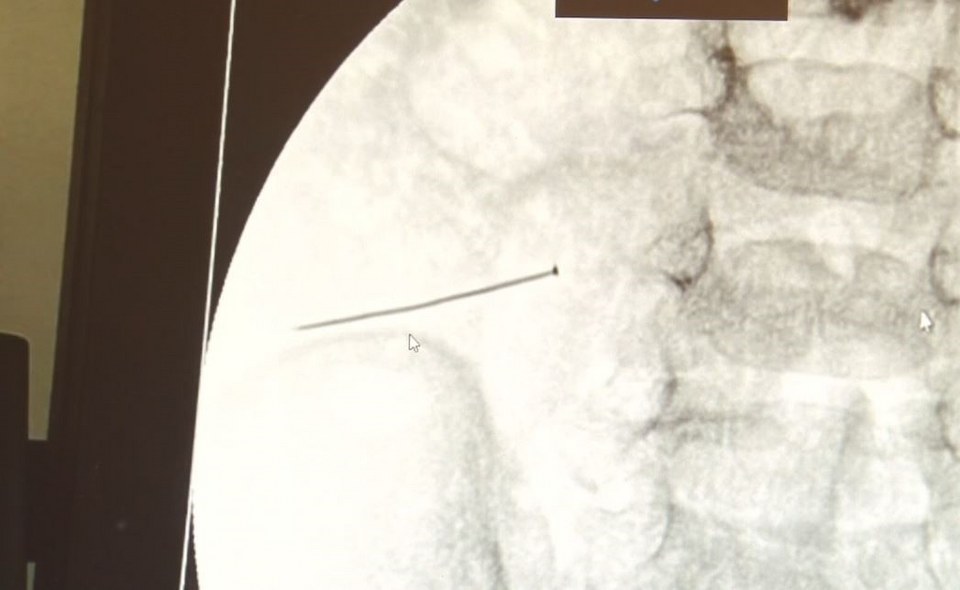

Öte yandan, yaklaşık 3 santimlik toplu iğne filme yansıyan görüntüsüyle gözler önüne serildi.

İstanbul’da 2 yaşındaki çocuk iddiaya göre toplu iğne yuttu sonrasında adeta karın ağrısıyla yerinde duramaz hale geldi. Babaanne, küçük çocuğun şikayetleri üzerine Şehit Prof. Dr. İlhan Varank Sancaktepe Eğitim ve Araştırma Hastanesi’ne götürdü. Burada yapılan tetkiklerde 2 yaşındaki çocuğun ince bağırsağında yaklaşık 3 santimlik toplu iğne olduğu ve bağırsağı deldiği belirlendi. Görüntülemeler sonrası 30 Ekim akşamı Çocuk Cerrahisi Kliniği Eğitim ve İdari Sorumlusu Doç. Dr. Sefa Sağ ve ekibi hemen ameliyata girdi. Başarılı operasyonla iğne olduğu noktadan alınırken aile de rahat bir nefes aldı. Doç. Dr. Sağ ise taburcu edilen hastasının durumuna ilişkin bilgi verirken yabancı cisim yutmalarına karşı ailelere önemli uyarılarda bulundu.

“Yaklaşık 3 santim toplu iğnenin ince bağırsağı deldiğini, içeriğin karın içerisine dolduğunu gördük”